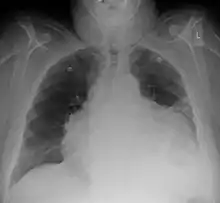

Chest x-ray: is non-specific and may not help identify a pericardial effusion but a very large, chronic effusion can present as "water-bottle sign" on an x-ray, which occurs when the cardiopericardial silhouette is enlarged and assumes the shape of a flask or water bottle.[2] Chest radiograph is also helpful in ruling out pneumothorax, pneumonia, and esophageal rupture.

A CT scan showing a pericardial effusion

Pericardial effusion due to malignancy. Note bulbous heart and primary lung cancer in right upper lobe.